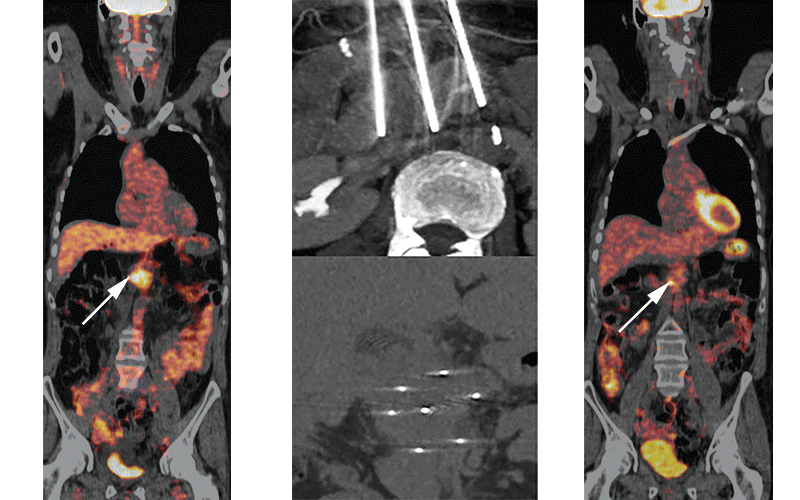

A, PET/CT showed an FDG-avid pancreatic tumor (arrow) in a 49-year-old that was successfully eradicated. B, no tracer uptake (arrow) was seen 18 months after IRE. C, During IRE, three needles surrounded the tumor (axiel view) and seven needles covered the entire tumor (coronal view). Ruarus AH, etal, Radiology 2020 ©RSNA 2020